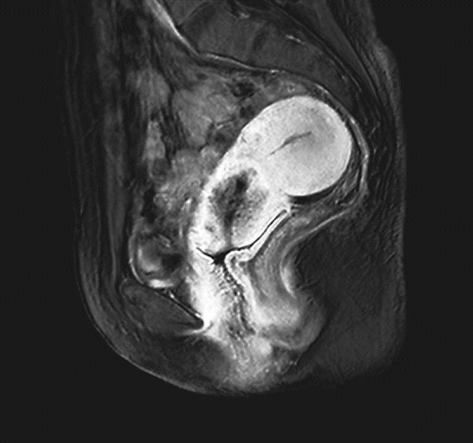

确诊后根据具体情况选择胸部X线或CT平扫、静脉肾盂造影、膀胱镜检査、直肠镜检查、超声检查及盆腔或腹腔增强CT或磁共振、PET-CT等影像学检查。

ⅠB1期宫颈癌MR ⅠB2期宫颈癌MR

ⅡA1期宫颈癌MR ⅡA2期宫颈癌MR

ⅡB期宫颈癌MR ⅢA期宫颈癌MR

ⅢB期宫颈癌MR ⅣB期宫颈癌MR